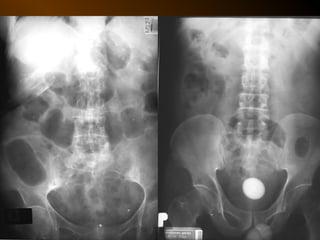

KHÍ TỰ DO

TRONG KHOANG PHÚC MẠC

NGUYÊN NHÂN

thủng tạng rỗng

nguồn gốc xuyên phúc mạc

nguồn gốc trong phúc mạc

10 – 15% thủng tạng rỗng → không thấy hơi tự do ổ bụng